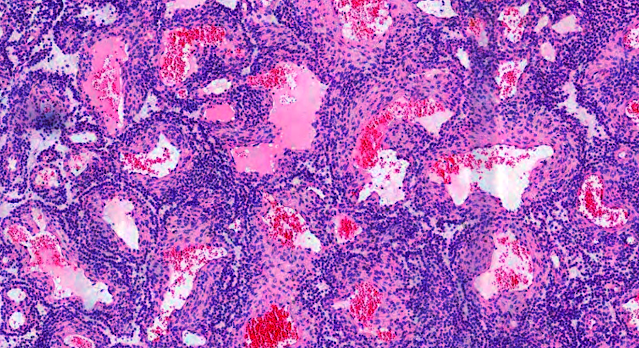

Dermatopathology Case 219 Get link Facebook X Pinterest Email Other Apps May 23, 2022 A 35 year old man with a nodule on the left middle finger. Answer Get link Facebook X Pinterest Email Other Apps Comments